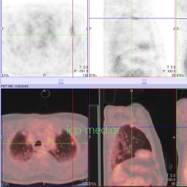

Images of PET/CT-findings of lesions, that had been false-positive for malignant tumours; pulmonary Tuberculosis (TBC) was diagnosed post Wedge Resection (excisional biopsy during Exploratory mini thoracotomy).

IMAGES 1-6: Solid mass (max. dim. 1.7 cm, SUVmax: 12) of the right lung (RLL) in a 50-yo male smoker’s case (50 pack-yrs).